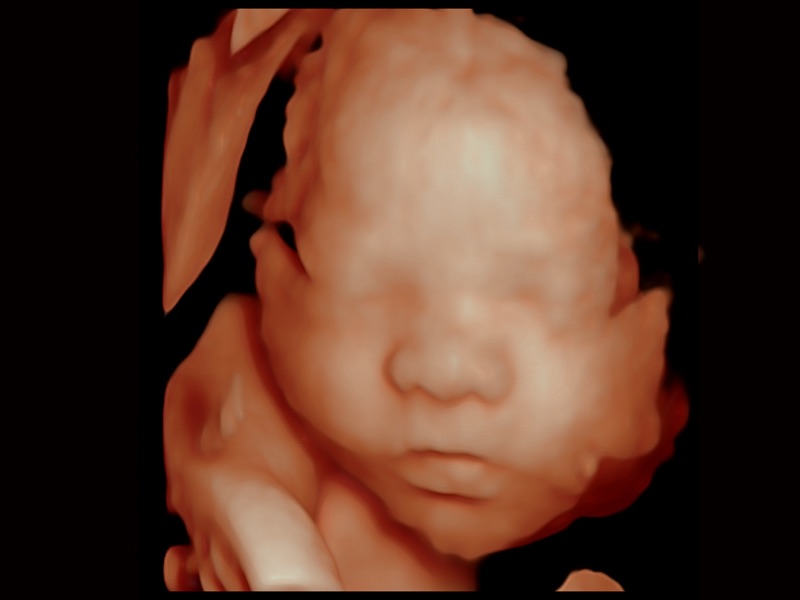

• 妇产科应用

临床图